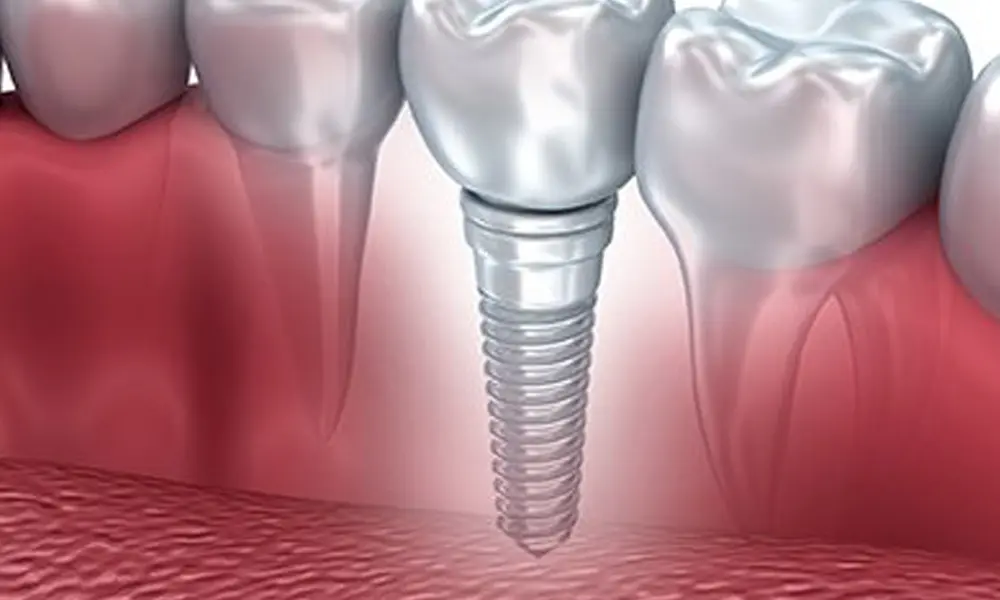

ایمپلنت دیجیتال یکی از جدیدترین و دقیقترین روشهای کاشت دندان است که با استفاده از فناوری سهبعدی، دقت جراحی را چند برابر میکند. در این روش، محل قرارگیری پایه ایمپلنت با کمک اسکن دهان و نرمافزارهای پیشرفته طراحی میشود تا نتیجه نهایی کاملاً طبیعی و بدون خطا باشد. اما یکی از سوالات پرتکرار بیماران این است: قیمت ایمپلنت دیجیتال چقدر است؟

هزینه ایمپلنت دیجیتال در تهران بسته به عوامل مختلفی مثل برند ایمپلنت، تعداد دندانهای جایگزینشده، نیاز به پیوند استخوان یا لثه، و تجربه متخصص متفاوت است. به طور کلی، قیمت این نوع ایمپلنت کمی بیشتر از روشهای سنتی است، اما در عوض، دقت بالا، درد کمتر، زمان جراحی کوتاهتر و دوران نقاهت سریعتر را برای شما به همراه دارد.

مزایای ایمپلنت دیجیتال در برابر هزینه آن بسیار چشمگیر است. شما نه تنها صاحب دندانی مقاوم و زیبا میشوید، بلکه به کمک فناوری سهبعدی، احتمال بروز عفونت یا آسیب به بافتهای اطراف به حداقل میرسد. همین ویژگیها باعث شده این روش به انتخاب اول بسیاری از بیماران و متخصصان در تهران تبدیل شود.

در روش ایمپلنت دیجیتال، محل قرارگیری پایهها با استفاده از اسکن سهبعدی و نرمافزارهای پیشرفته تعیین میشود؛ به همین دلیل خطای انسانی تقریباً به صفر میرسد و روند جراحی بسیار سریع و بدون درد انجام میشود. دکتر مرتضی قادری با تسلط کامل بر این فناوری و استفاده از تجهیزات مدرن، تجربهای متفاوت از ایمپلنت برای بیماران خود فراهم میکند.

ایمپلنت دیجیتال یکی از مدرنترین و دقیقترین روشهای جایگزینی دندانهای از دست رفته است. در این روش، با کمک فناوریهای پیشرفته مانند اسکن سهبعدی (3D Scan)، نرمافزارهای طراحی دیجیتال و راهنمای جراحی دقیق، ایمپلنت با بیشترین دقت ممکن در استخوان فک قرار میگیرد. اما یکی از سوالاتی که همواره ذهن بیماران را درگیر میکند، این است که عمر ایمپلنت دیجیتال چقدر است؟

واقعیت این است که اگر ایمپلنت توسط متخصص با تجربه و حرفهای انجام شود و مراقبتهای پس از درمان به درستی رعایت گردد، عمر ایمپلنت دیجیتال میتواند بیش از ۲۰ تا ۲۵ سال و حتی مادامالعمر باشد. جنس تیتانیومی پایه ایمپلنت به گونهای طراحی شده که با استخوان فک به صورت طبیعی جوش میخورد و در برابر فشارهای جویدن و تحلیل استخوان مقاومت بسیار بالایی دارد..اگر به دنبال کاشت دندانی بادوام، طبیعی و هماهنگ با فرم لبخندتان هستید، مراجعه به مراکز ایمپلنت دندان در تهران میتواند هوشمندانهترین انتخاب شما باشد.

یکی از مهمترین مزیتهای ایمپلنت دیجیتال در مقایسه با روش سنتی، دقت بالای کاشت و کاهش احتمال خطا است. در جراحی دیجیتال، محل دقیق کاشت ایمپلنت پیش از جراحی طراحی میشود و این موضوع باعث میشود فشار غیرطبیعی به استخوان یا لثه وارد نشود. همین دقت بالا موجب میشود پایه ایمپلنت بهتر در استخوان فک تثبیت شود و در نتیجه طول عمر ایمپلنت دیجیتال بیشتر از روشهای معمولی باشد.